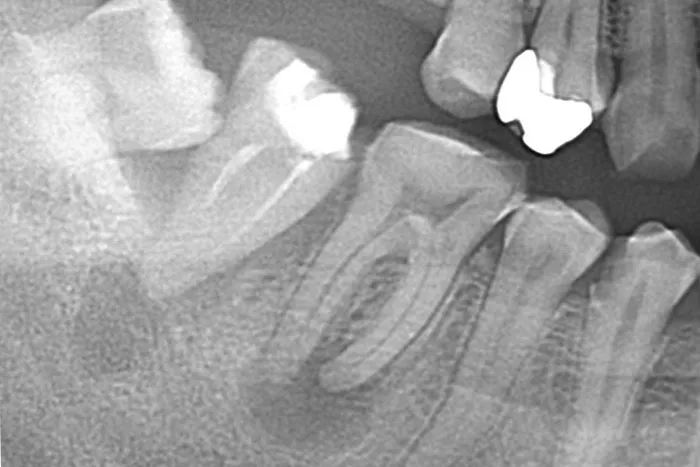

症例① 右の下の歯が痛んで

食べ物が噛めない

Before

After

| 主訴 | 右の下の歯が痛んで食べ物が噛めない |

|---|---|

| 治療期間 | 2ヶ月 |

| 治療費 | 国民健康保険の範囲内 |

| 治療内容 | 根管治療 |

| 治療のリスク | 根管治療中の炎症による痛み |

▲治療のコメント

根管治療の成否は、感染源の除去と感染経路の封鎖の両方が出来ることが大事になります。

今回のケースでは、根の先に大きな膿の袋がありましたが、感染源である虫歯の除去・根幹内の洗浄・親知らずのポケットからの感染経路を遮断することが出来たので治癒したと考えています。